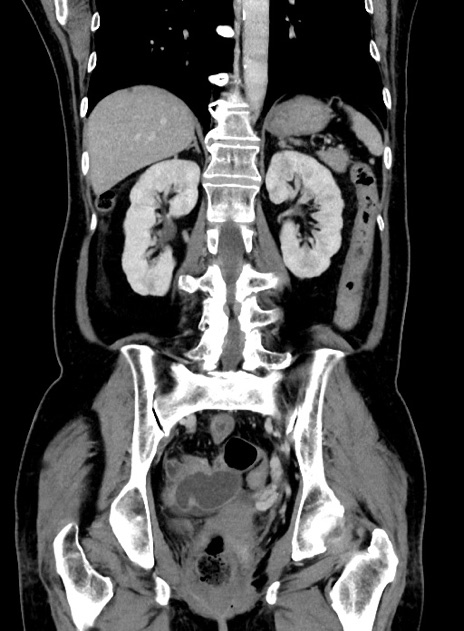

症例9(冠状断像)

【症例】 60歳代女性

【主訴】むかつき、みぞおちの痛み

【現病歴】3日前よりむかつきがあり、食事がとれない。

【既往歴】糖尿病

【身体所見】発熱なし、心窩部圧痛軽度あるも、腹膜刺激症状なし。

【データ】WBC 7400、CRP 1.92

横断像